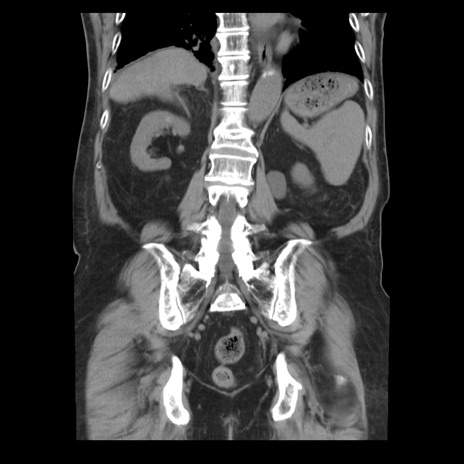

症例21(冠状断像)

【症例】70歳代男性

【主訴】腹痛

【現病歴】肝硬変・肝細胞癌にてかかりつけの方。約9時間前に食後より腹痛出現。症状が徐々に増悪し、嘔吐出現したため来院。

【既往歴】肝硬変、肝細胞癌(RFA、TACE後)

【身体所見】意識清明、表情苦悶様、BT 36℃、BP 129/78mmHg、P 88bpm、SpO2 97%(RA)、右上腹部から心窩部にかけて圧痛あり、反跳痛なし、筋性防御あり。

【データ】WBC 5800、CRP 0.16